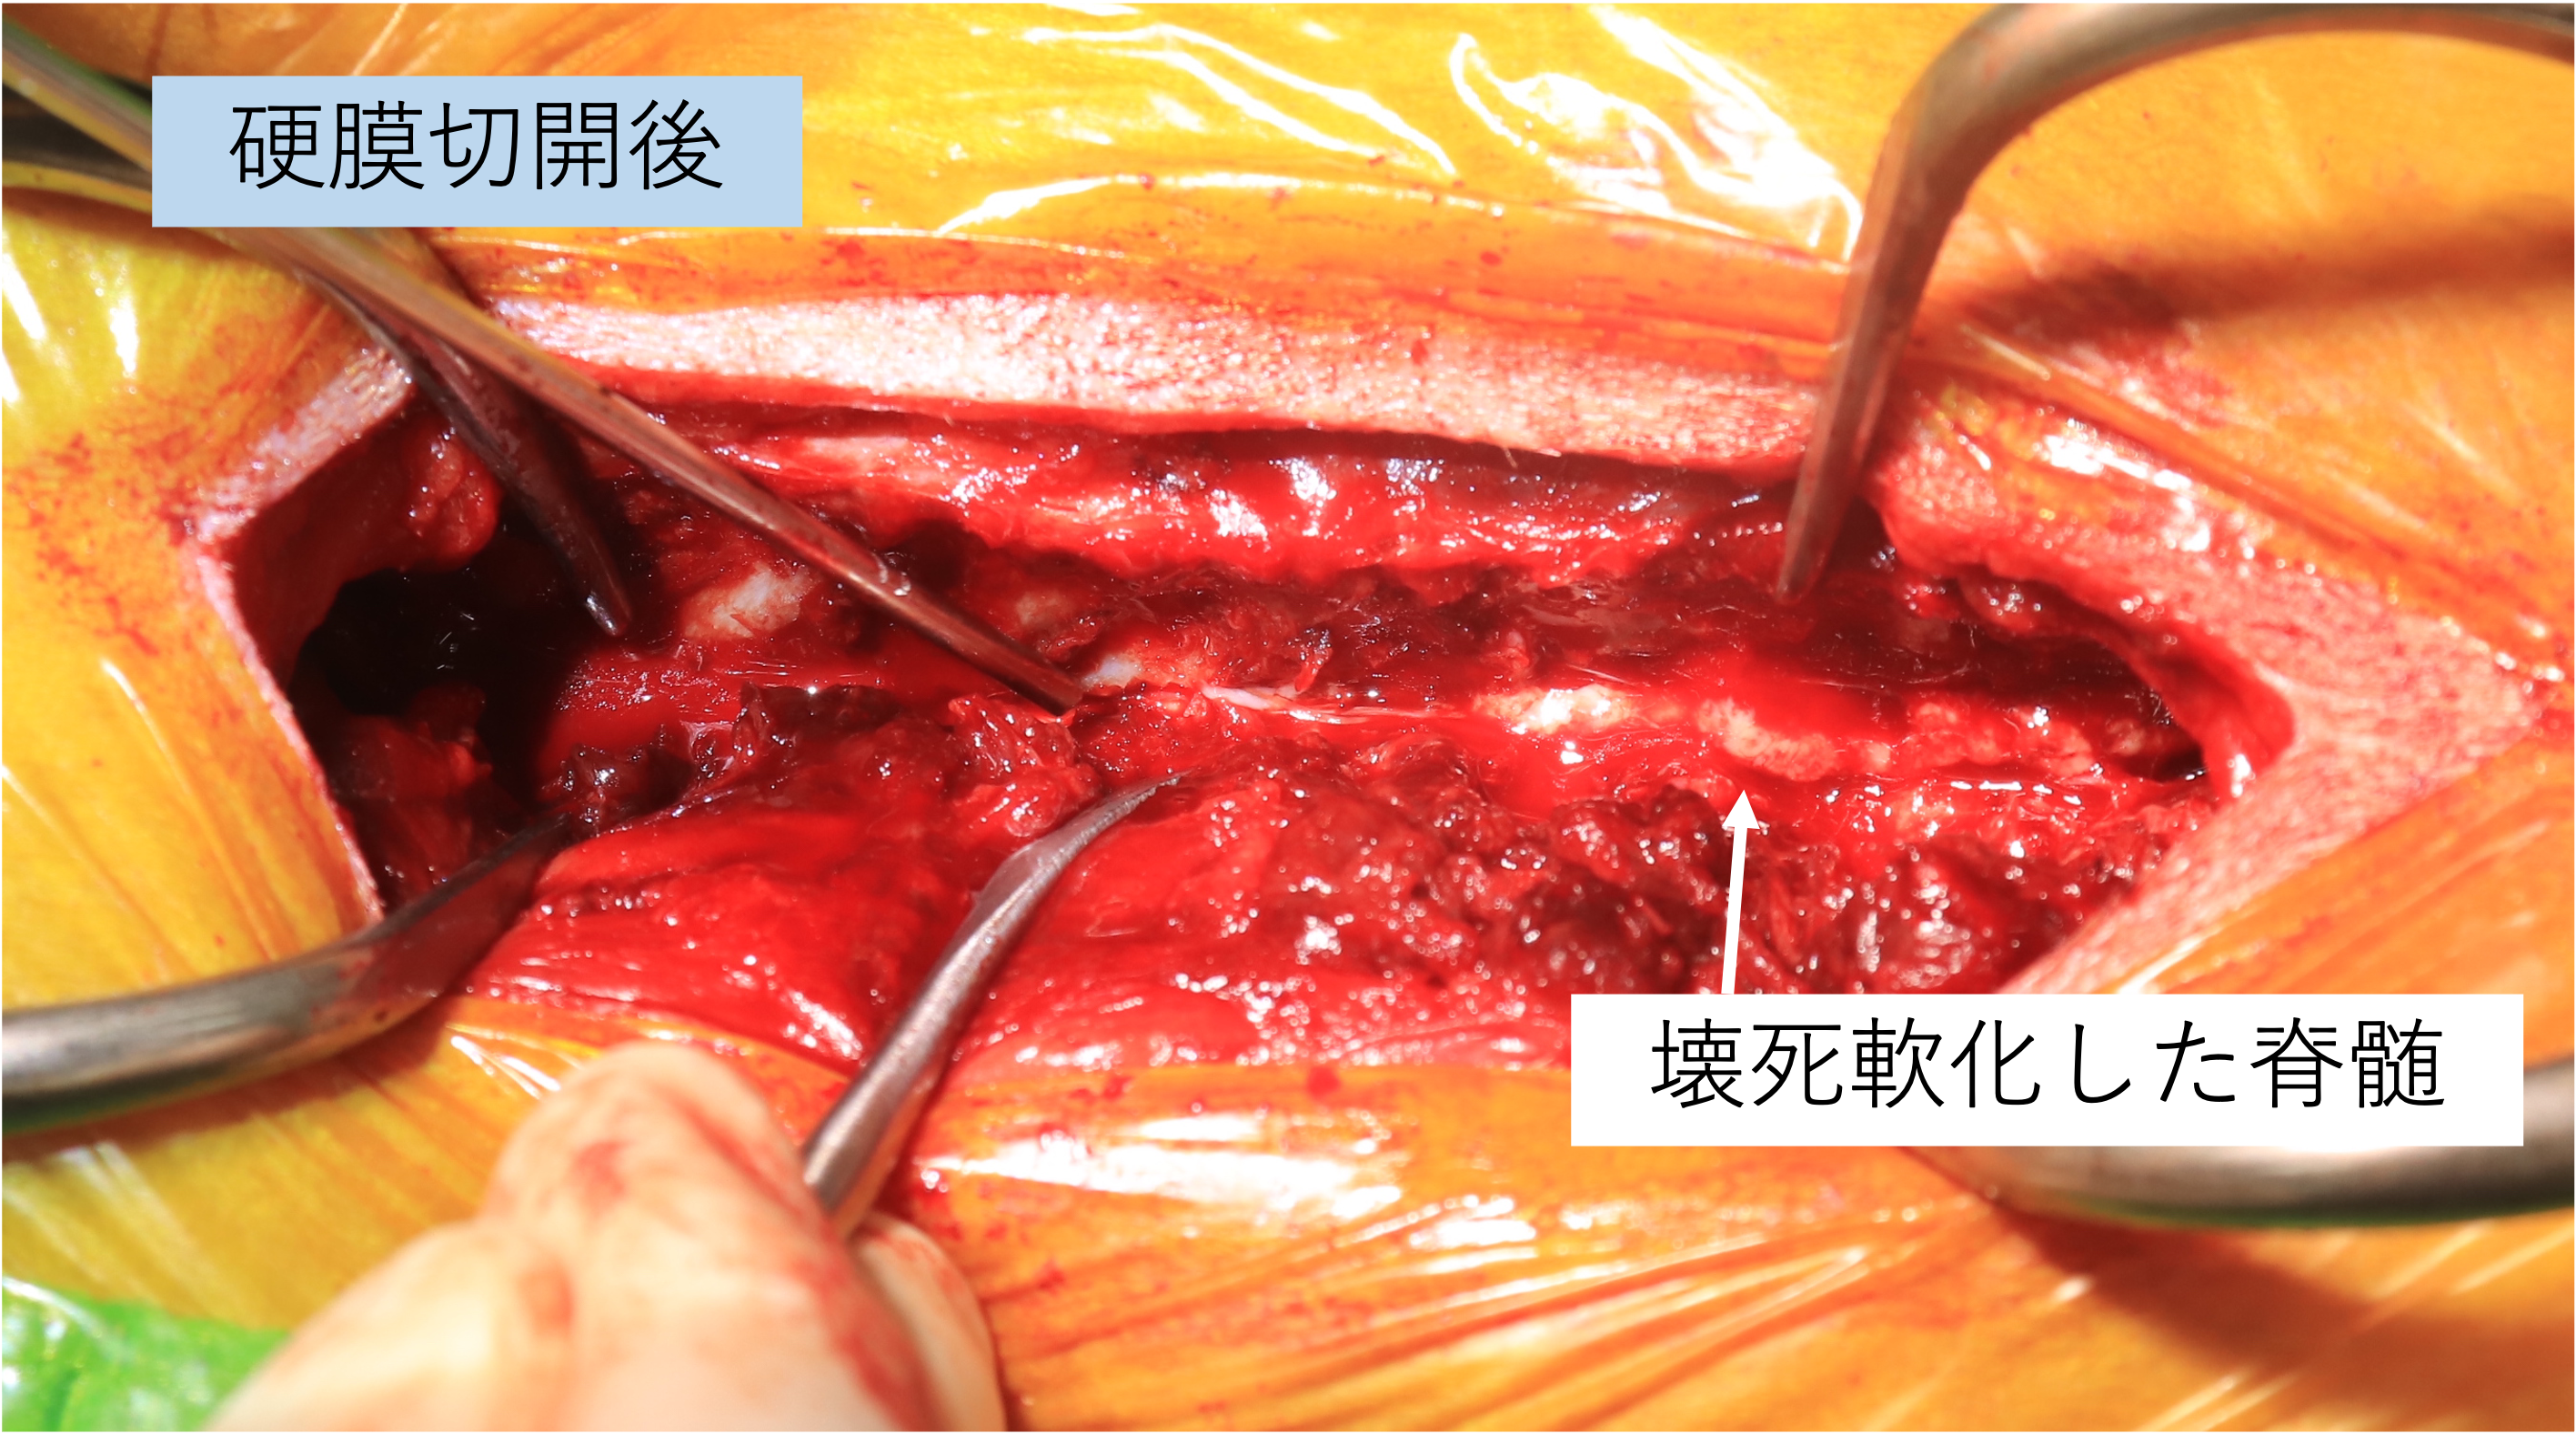

8才7ヶ月齢ミニチュアダックスフンド グレード5のT12-13椎間板ヘルニアです。病変部からT8までの脊髄はT2強調で高信号を呈しており、画像上、脊髄軟化症が強く疑われました。即日手術となり片側椎弓切除を実施したところ、硬膜には発赤が認められました。硬膜切開を実施したところ脊髄は軟化しており、後に病理組織検査で脊髄軟化症と診断されました

従来、脊髄軟化症は進行性であり、3-10日ほどの経過で100%死亡するとされていますが、近年、拡大的な減圧術を行うことにより救命可能となった症例が少しずつ蓄積されております。本症例においても拡大的椎弓切除+硬膜切開を行いました。T7よりも頭側の脊髄は肉眼的に正常な脊髄でした